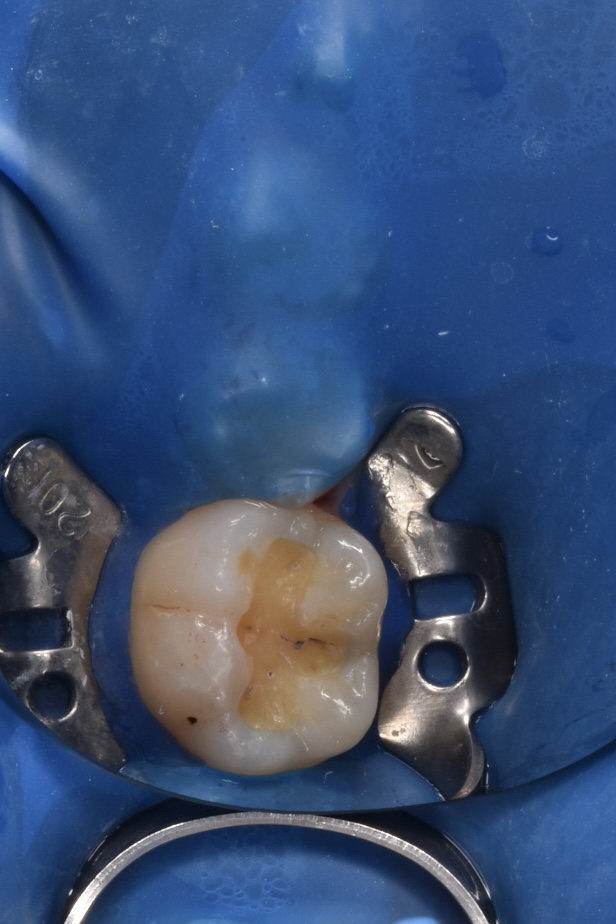

治療プロセス(自由診療のみ適応しているものもあります)